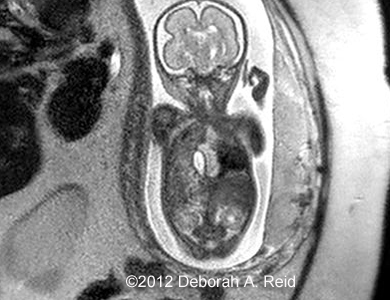

The left-sided congenital diaphragmatic hernia contained a large portion of the bowel, spleen, stomach and the tip of the left lobe of the liver. In addition to the congenital diaphragmatic hernia, a sub-diaphragmatic sequestration was also noted which was confirmed by MRI.

Figure 11: MRI confirmed the diagnosis

CDHMRI1